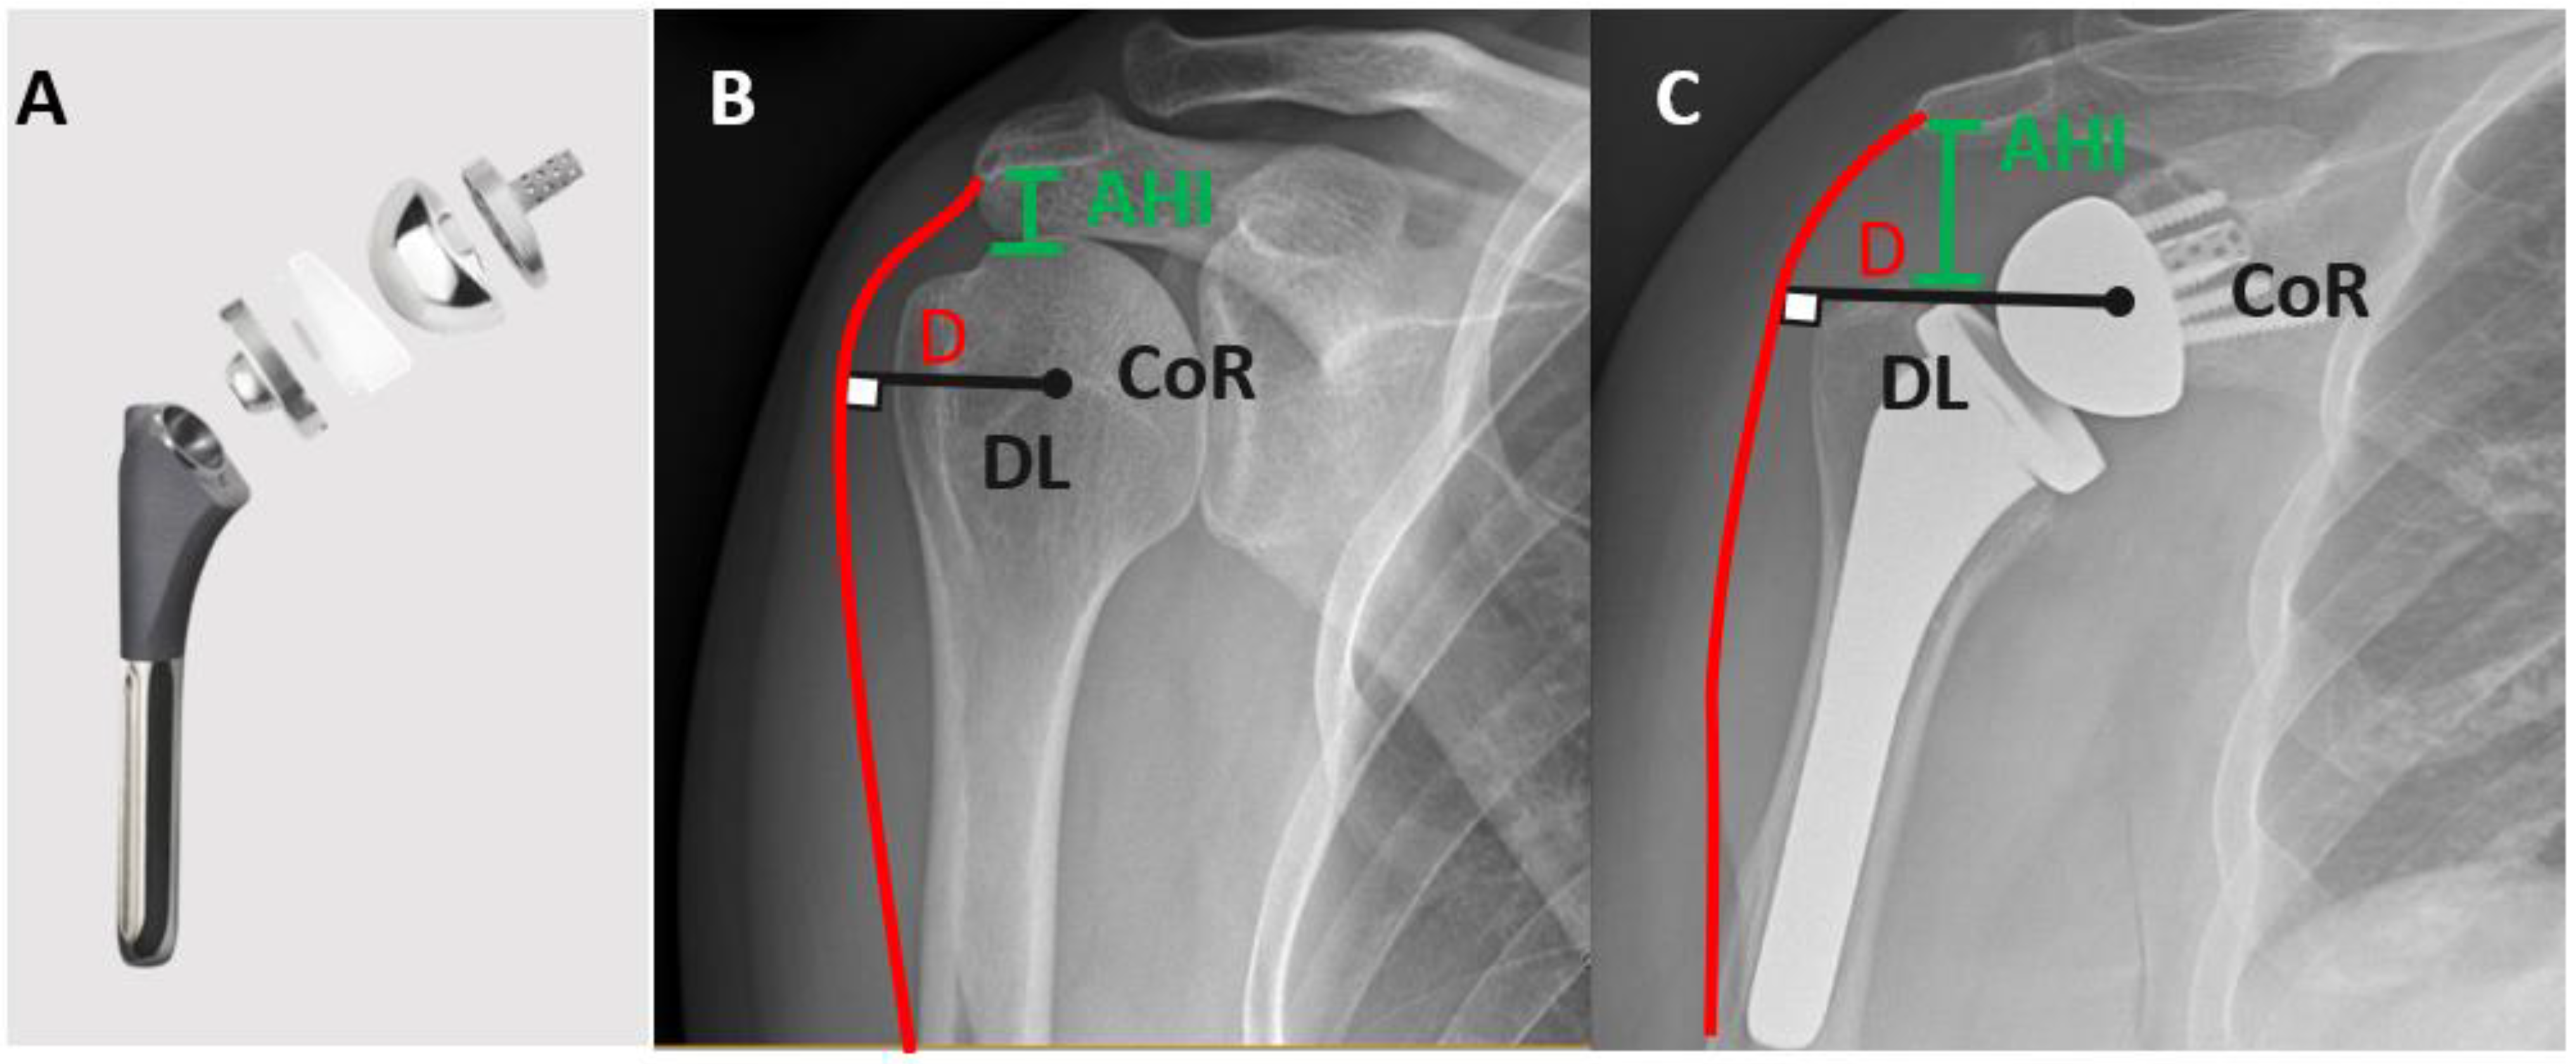

7.2. Standard Humeral Stem versus Fracture Stem